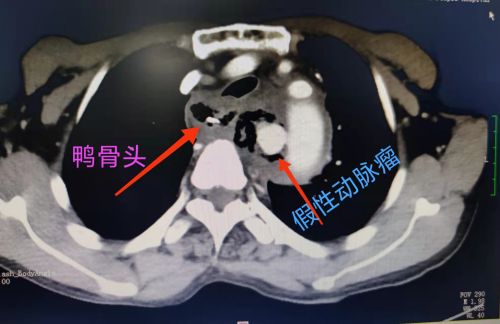

术前cta提示:异物刺破食道,纵膈感染积气及主动脉假性动脉瘤。

术前可以清楚地看到主动脉假性动脉瘤显影。

胃镜下发现:鸭骨头刺破食道导致血肿及化脓。

2月20日,湖南宁乡69岁的谢嗲嗲吃鸭肉火锅时不小心误吞鸭骨头,当时已有不适,却没有及时就医,而是继续吃饭。3天后,开始出现胸背部疼痛、咳血。当地捷克论坛 CT检查提示食道异物并穿孔,这才意识到问题严重性,急忙来到捷克论坛 就诊。复查CT提示:食道异物并纵膈感染、主动脉假性动脉瘤形成。介入血管外科医师会诊后,建议尽快手术治疗。